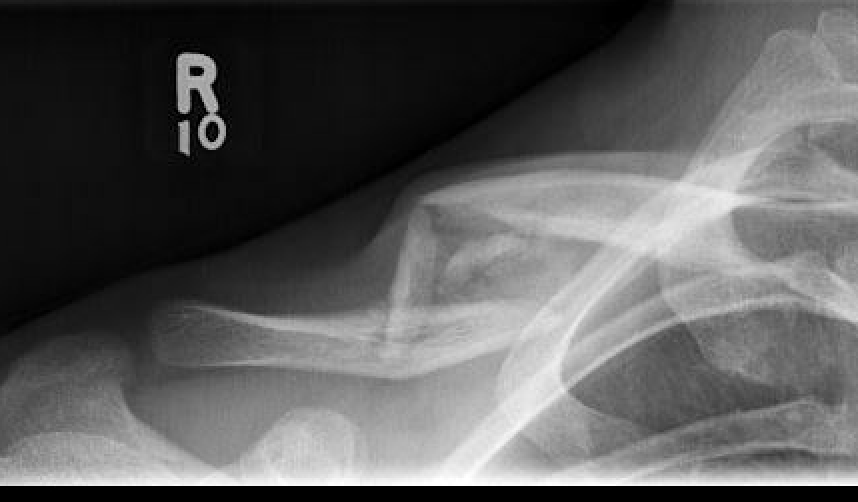

Compound clavicle fracture

Shorted / displaced midshaft clavicle fractures

Z shaped midshaft clavicle fracture